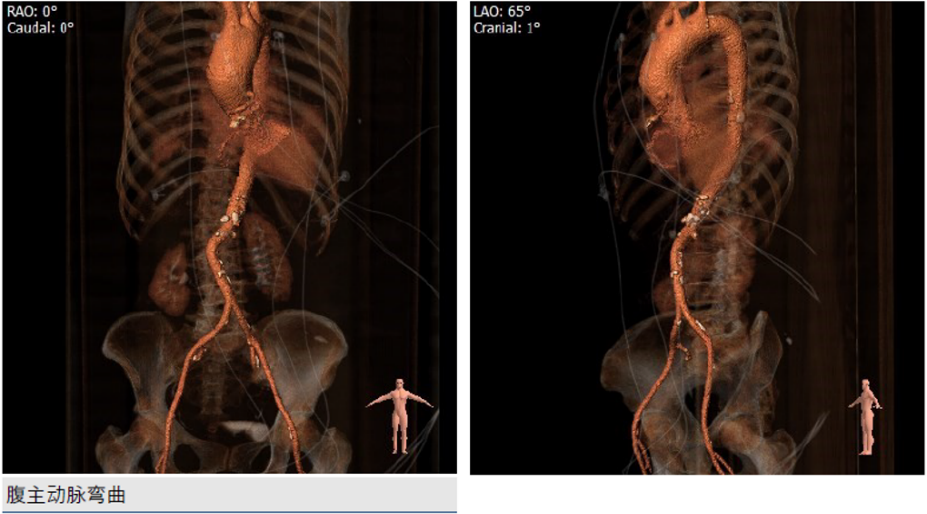

2、腹主动脉迂曲,升主动脉增宽;

CT分析:

根据测得的瓣环直径,结合患者二叶式主动脉瓣,瓣叶见钙化,以及畸形的有效开口,术中决定采用Evolut PRO 23mm瓣膜。递送系统顺利过弓跨瓣,球囊预扩后目标深度开始释放,得益于可回收设计,术中再回收进行一次位置调整,最终目标位完美释放,瓣膜立即工作,展开形态良好,无冠脉阻挡,无传导阻滞发生,术后压差<10mmHg,血流动力学稳定,手术圆满成功。